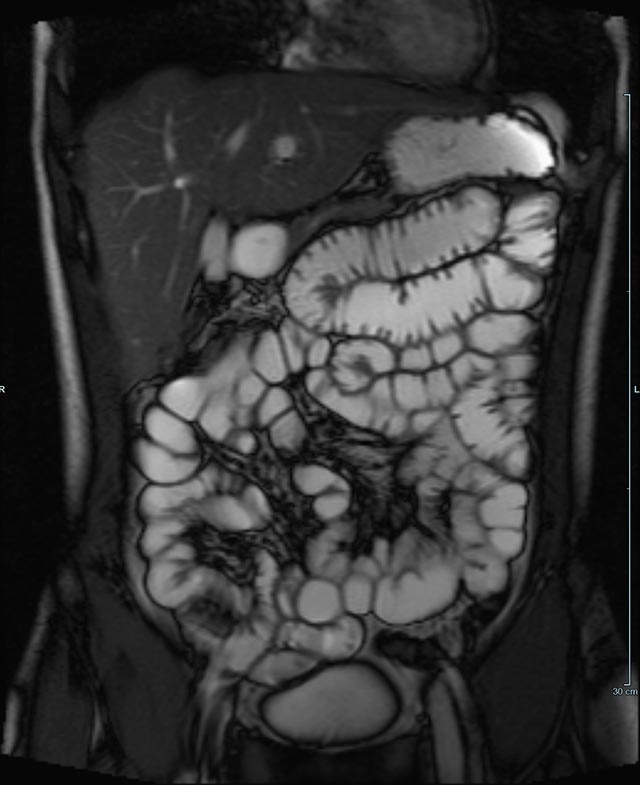

- Dünndarm/Dickdarm

- Chronisch-entzündliche Darmerkrankungen wie Morbus Crohn oder Colitis ulcerosa. Beurteilung der Ausdehnung der Entzündung, Darstellung von Fisteln oder Abszessen bzw. einer Passagebehinderung (MR-Sellink, MR-Kolonographie, beide Untersuchungen nach spezieller Vorbereitung)

- Darstellung bzw. Kontrolle im Verlauf bei perianalen Fisteln und Abszessen

- Verlaufskontrolle des Lokalbefundes nach Rektumentfernung bei Karzinom